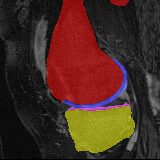

Knee MRI experiment: We test our method on 3D knee MRIs from the Osteoarthritis Initiative (OAI) 111https://nda.nih.gov/oai/ and corresponding segmentations of femur and tibia as well as femoral and tibial cartilage [1]. From a total of 507 labeled images, we use 200 for training, 53 for validation, and 254 for testing. To test registration performance we use 10,000 random image pairs from the test set. All images are affinely registered to an atlas built from the training images, resampled to isotropic spacing of 1mm, cropped to and intensity normalized to [0,1]. In addition, right knee images are flipped to be consistent with left knees. For training, the loss weights are , , and based on approximate hyper-parameter tuning. Note that when computing from the displacements, the image coordinates are scaled to [-1, 1] for each dimension following the convention in the interpolation function of PyTorch.

Results: All trained networks are evaluated using Dice overlap scores between predictions and the manual segmentations for the segmentation network, or between the warped moving segmentations and the target segmentations for the registration network. Tabs. 1 and 2 show results for the knee and brain MRI experiments respectively in Dice scores (%). Fig. 2 shows examples of knee MRI registrations and brain MRI segmentations.

Knee results: On knee MRIs, our method improves segmentation scores over separately learned networks by about 1.2 and 0.5, and registration scores increase by about 3.1 and 3.0, when training with 5 and 10 manual segmentation respectively. Especially for the challenging cartilage structures, our joint learning boosts segmentation by 1.4 and 0.7, and registration by 5.5 and 5.2 for N=5 and N=10 respectively.

Qualitative results: DA achieves more anatomically consistent registrations than the mono-networks on the knee (Fig. 2) and Brain MRI samples (see supplementary material).